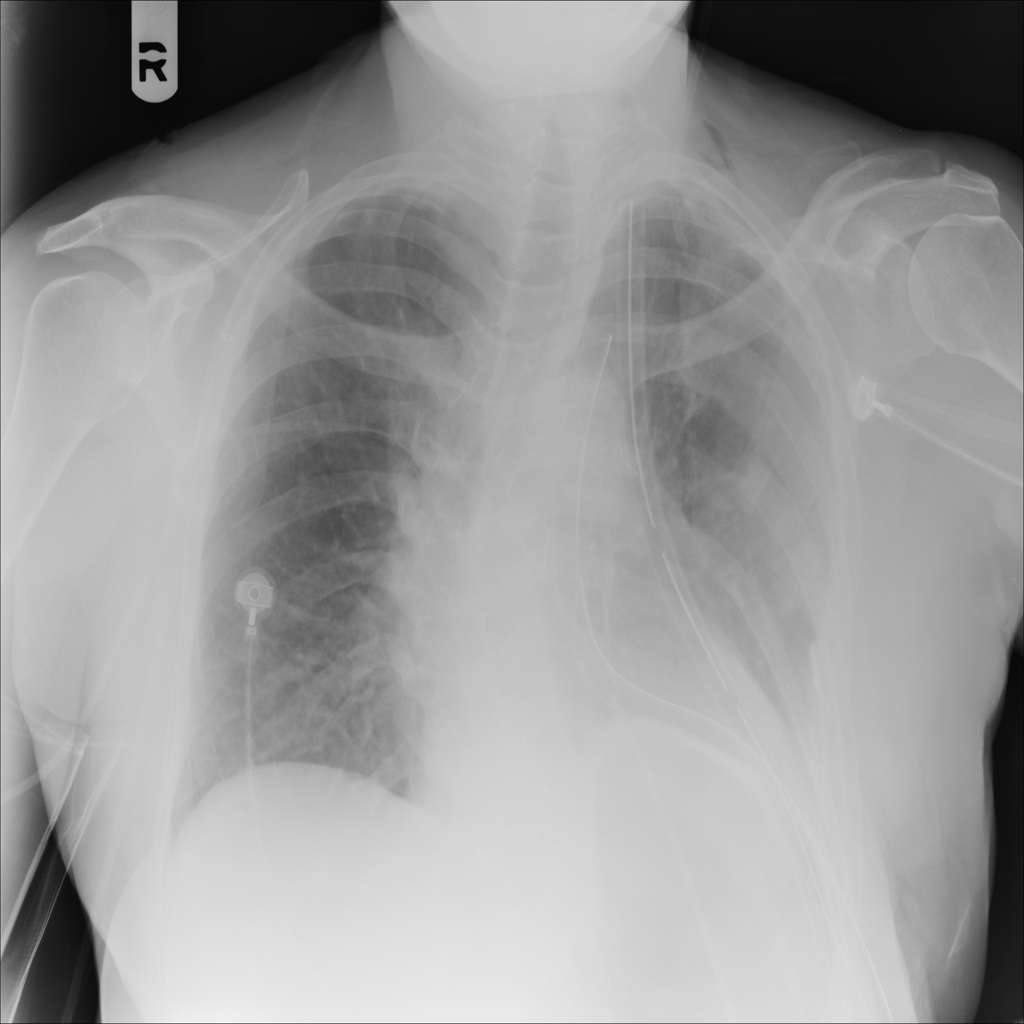

PAT-3DB4 · IMG-001Emphysema

PAT-3DB4 · IMG-001

PA